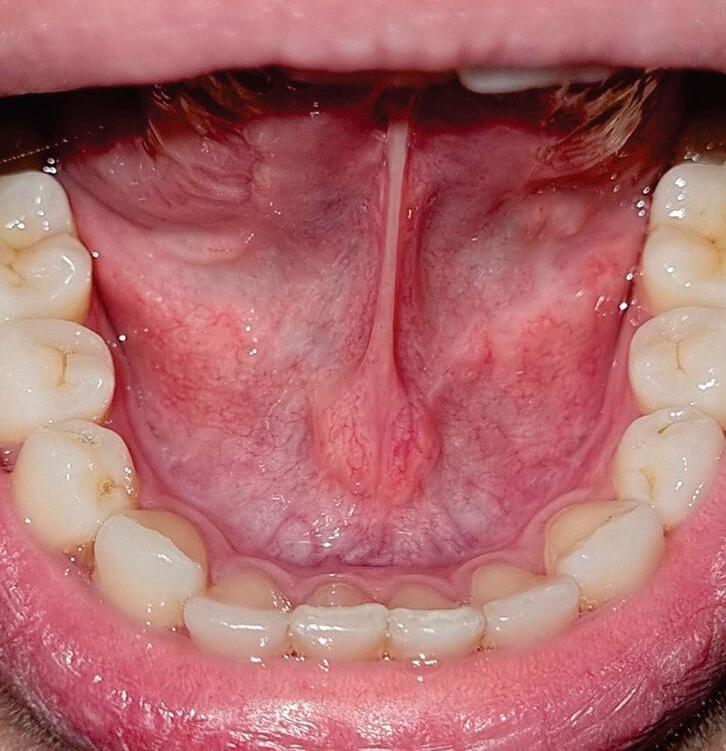

Ao descrever a língua, utilizamos os termos dorso, ventre e bordas para caracterizar as regiões superior, inferior e laterais, respectivamente. Os dois terços anteriores da língua, ou corpo da língua, é uma região com característica de alta mobilidade. O terço posterior da língua, ou base da língua, é menos móvel, porque está preso ao assoalho da boca e estende-se até a faringe. De forma geral, a base da língua não é visível durante

o exame de rotina. A superfície dorsal da língua é recoberta por uma grande quantidade de papilas linguais, as filiformes e fungiformes. A língua deve ser cuidadosamente examinada tracionando-a com auxílio de gaze. Mais posteriormente, uma estrutura em forma de "V" invertido é chamada de sulco terminal e, em sua interseção, encontramos o forame cego. Anteriormente ao sulco terminal são encontradas as papilas valadas ou circunvaladas. As papilas foliadas

são áreas bilateralmente simétricas de vermelho-rosado localizadas no terço posterior das bordas linguais. A inspeção da língua deve ser concluída pedindo-se ao paciente que a eleve a fim de se inspecionar a superfície ventral. O ventre é formado por uma mucosa fina, brilhante e translúcida, revelando numerosos vasos sanguíneos, especialmente as duas veias linguais que correm paralelamente em ambos os lados da linha média (Fig. 1-5).

Fig. 1-5. (a) dorso de língua. Observar presença das papilas filiformes e fungiformes. (b) Borda de língua do lado direito. Observar limite superior de uma mucosa mastigatória com limite inferior de mucosa de revestimento não queratinizada. (c) Ventre da língua. Observar a presença do freio lingual em sua posição habitual.

glândulas sublinguais e posteriormente, em uma topografia abaixo do diafragma muscular, encontram-se as glândulas submandibulares. O freio lingual é uma dobra de tecido na linha média que vai da superfície ventral da língua, passando pelo soalho da boca e inserindo-se na gengiva lingual entre os dois incisivos centrais inferiores. Lateralmente ao freio lingual estão as carúnculas sublinguais, que representam as aberturas dos ductos das glândulas submandibulares. O soalho deve ser avaliado por palpação bimanual digitopalmar, em que se posiciona a polpa do dedo indicador intraoralmente e a palma da outra mão extraoralmente sob o mento (Fig. 1-6).

Fig. 1-6. soalho bucal. mucosa de revestimento brilhante e lisa. Observar, lateralmente ao freio lingual, a presença das carúnculas sublinguais.